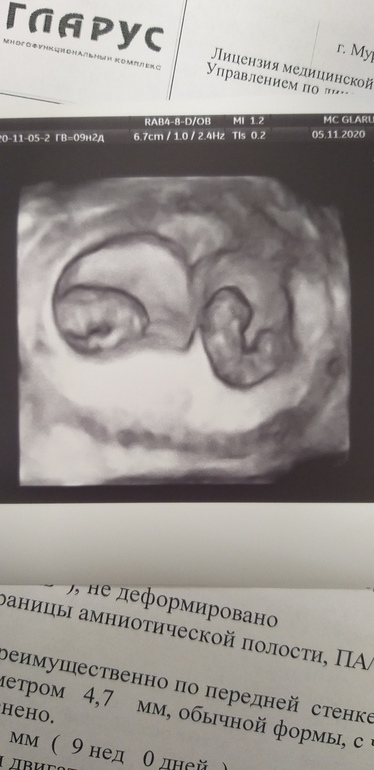

Я уже привыкла их ди-ди называть 🙃 фото вчерашнее ,9 неделек и 2 дня ❤

Малыши потрясные)))

Диди у вас) жт или рассосалось или клеточка рано поделилась. Какое чудесное фото😍 Когда малыши креветочки - так все ещё хорошо можно разглядеть))

У них уже есть ручки, ножки. Видно хорошо было на 2 Д, это 3 Д фото удачно двоих поймали.